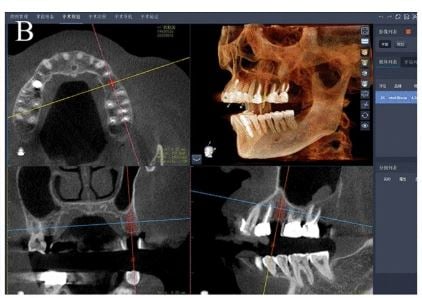

This patient presents with periimplantitis of the lower left quadrant. Removal of existing implants with Guided Bone Regeneration is required. The tent pole technique for GBR was used.